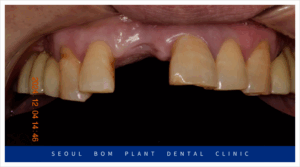

위턱 오른쪽 앞니(#11)의 경우

환자분과 충분한 상담을 통해

양옆의 치아를 이용한

브릿지 보철물을

진행하기로 계획하였는데요.

기존 임플란트가 빠지고

잇몸뼈가 소실이 심한 상태라

잇몸뼈가 어느 정도 찰 때까지

충분한 시간을 가지고

진행하기로 하였으며,

심미성이 중요한 앞니이다 보니

일상생활에 있어 불편감을

덜어드리기 위해

wire temporary 제작하여

사용하실 수 있도록

도와드리기로 하였습니다.

양측 위아래 어금니의

임플란트 보철물이 마무리되고 나서

앞니 심미보철치료를 진행하였는데요.

앞니는 심미성이 중요한

부위이다 보니 치아를 다듬기 전

환자분과 함께 색상과 모양을

꼼꼼하게 확인하는 작업을 거쳤으며

보철물 수복에

필요한 만큼의 양만 삭제하여

신경치료 없이 진행을 하였습니다.

앞니도 어금니와 마찬가지로

심미성이 높은 지르코니아

보철물로 수복해 드리면서

모든 치료를 마무리해 드렸는데요.